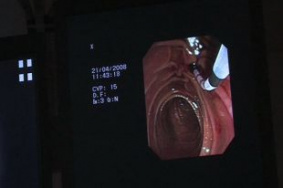

Полипы в кишечнике. Как не пропустить первые симптомы